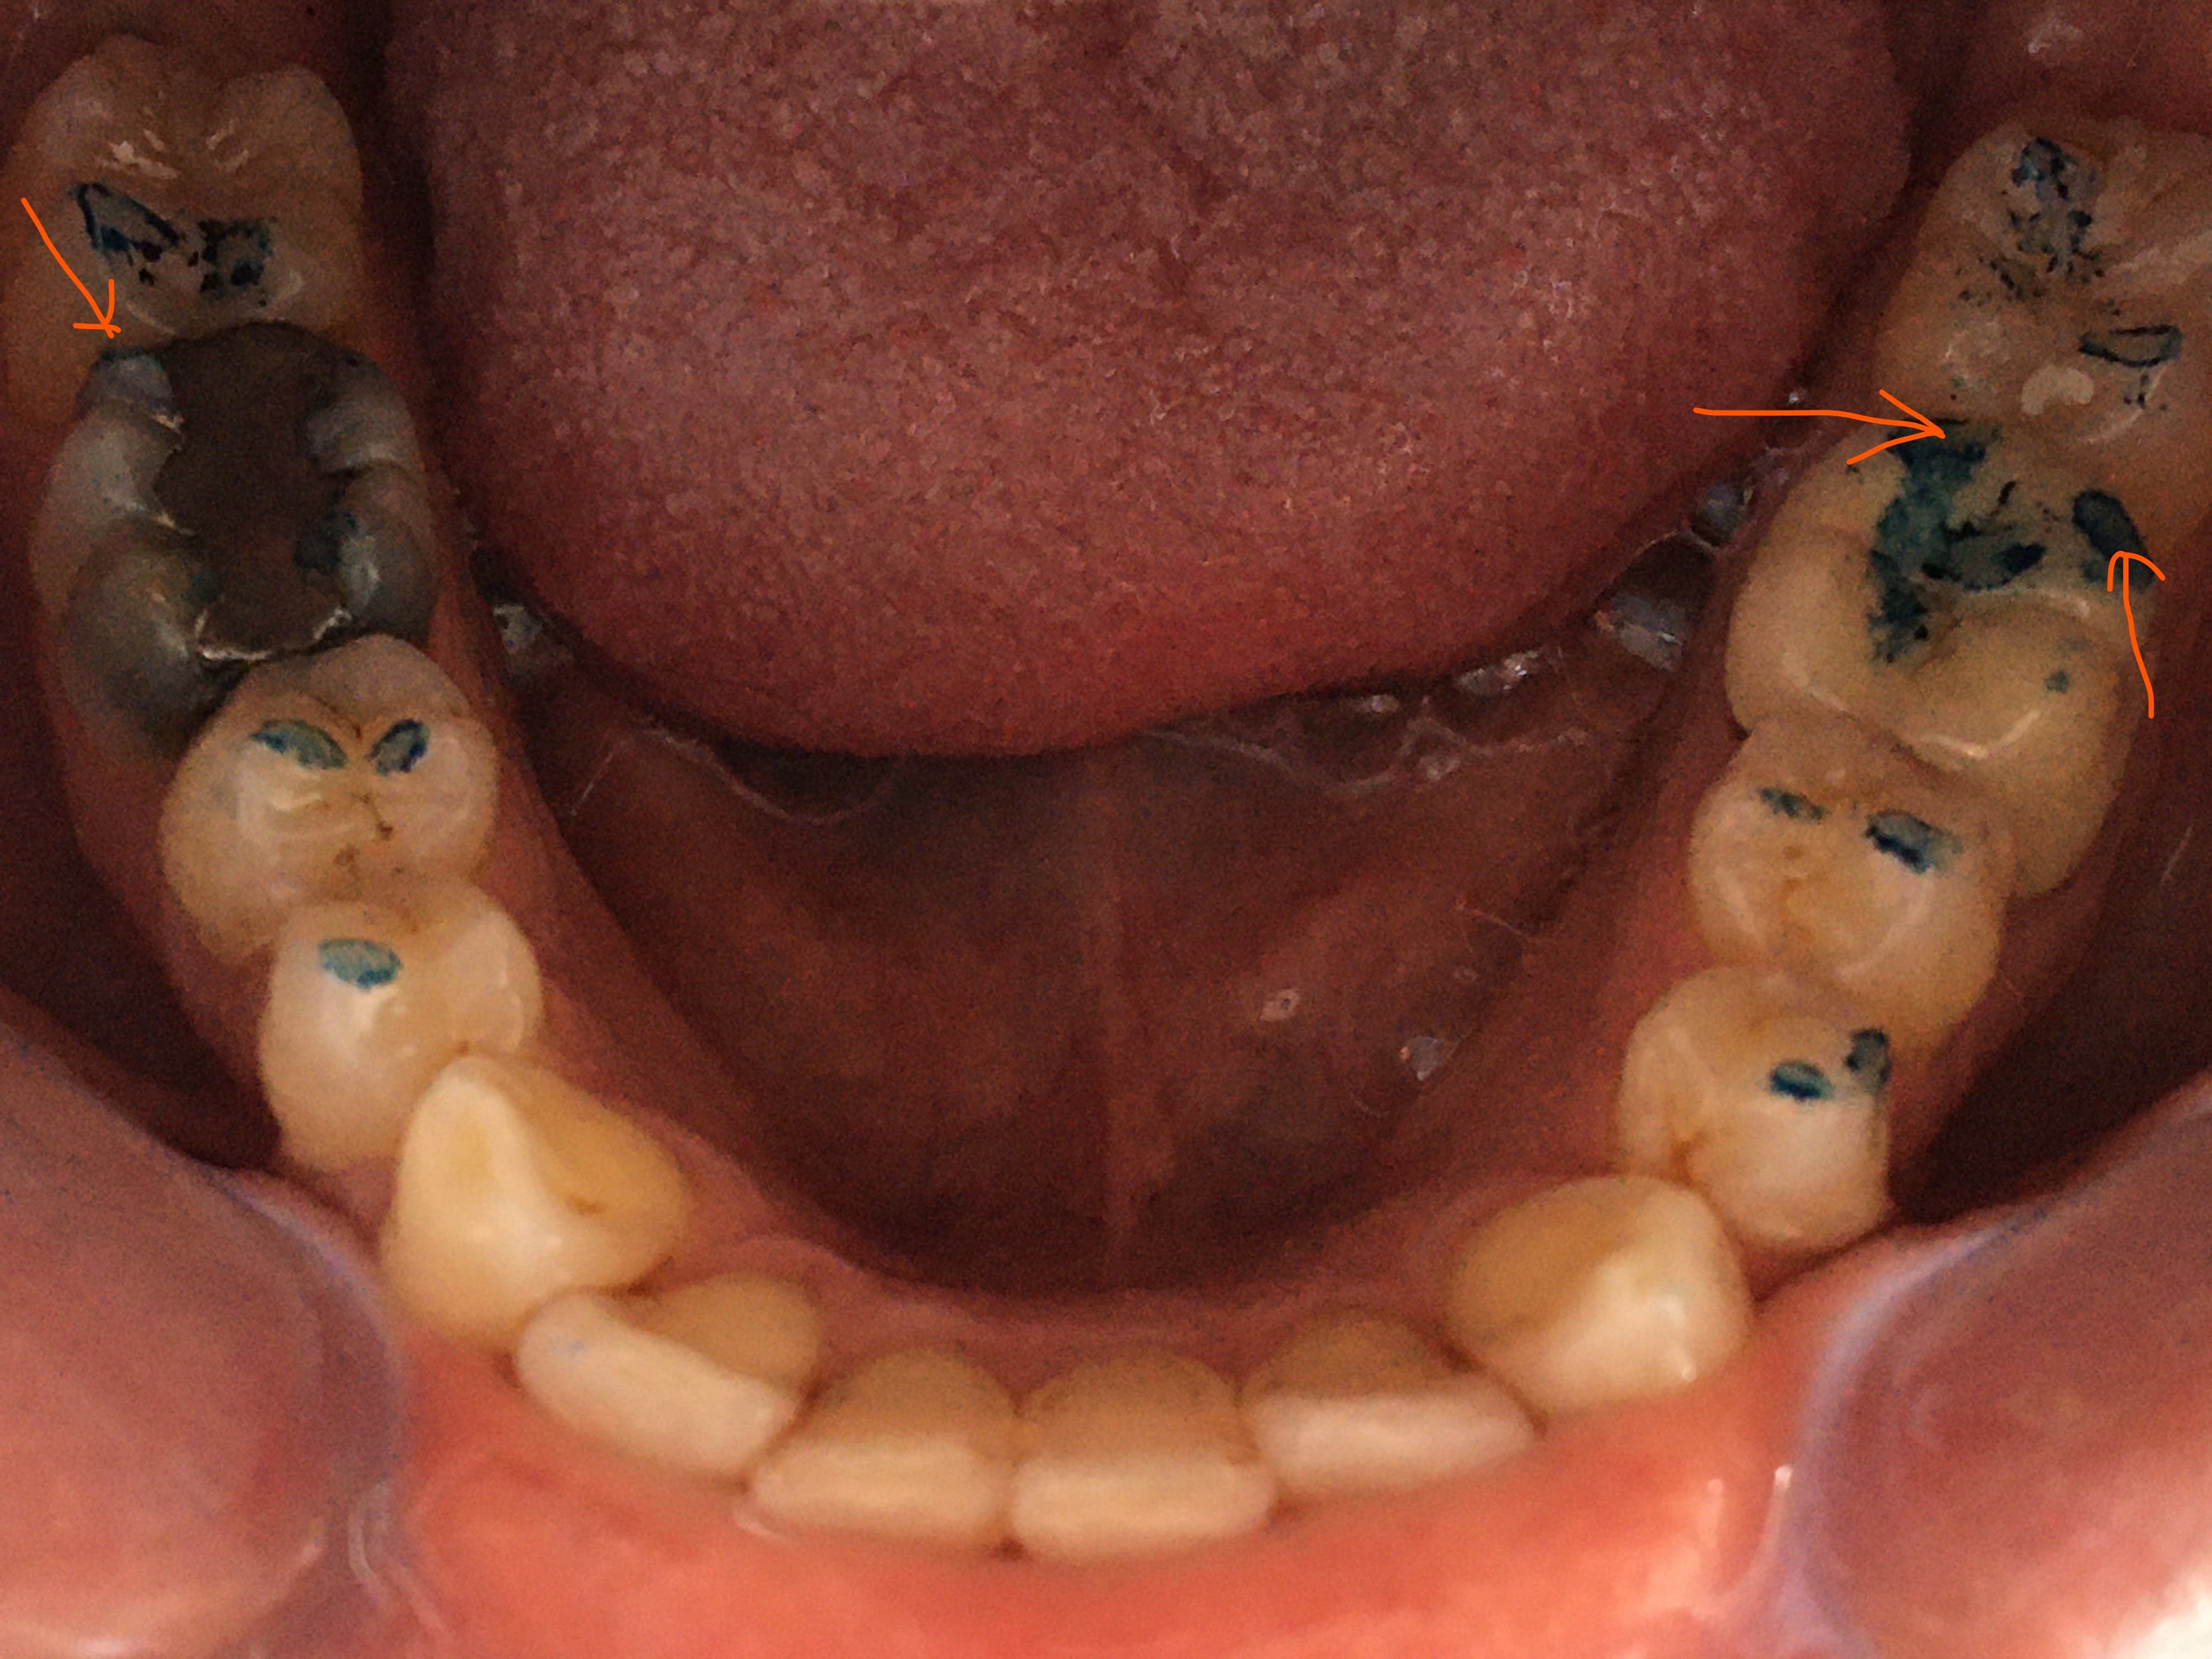

Photos vites faites Contacts en oim

On dirait bien une grosse surocclusion sur la coiffe 36